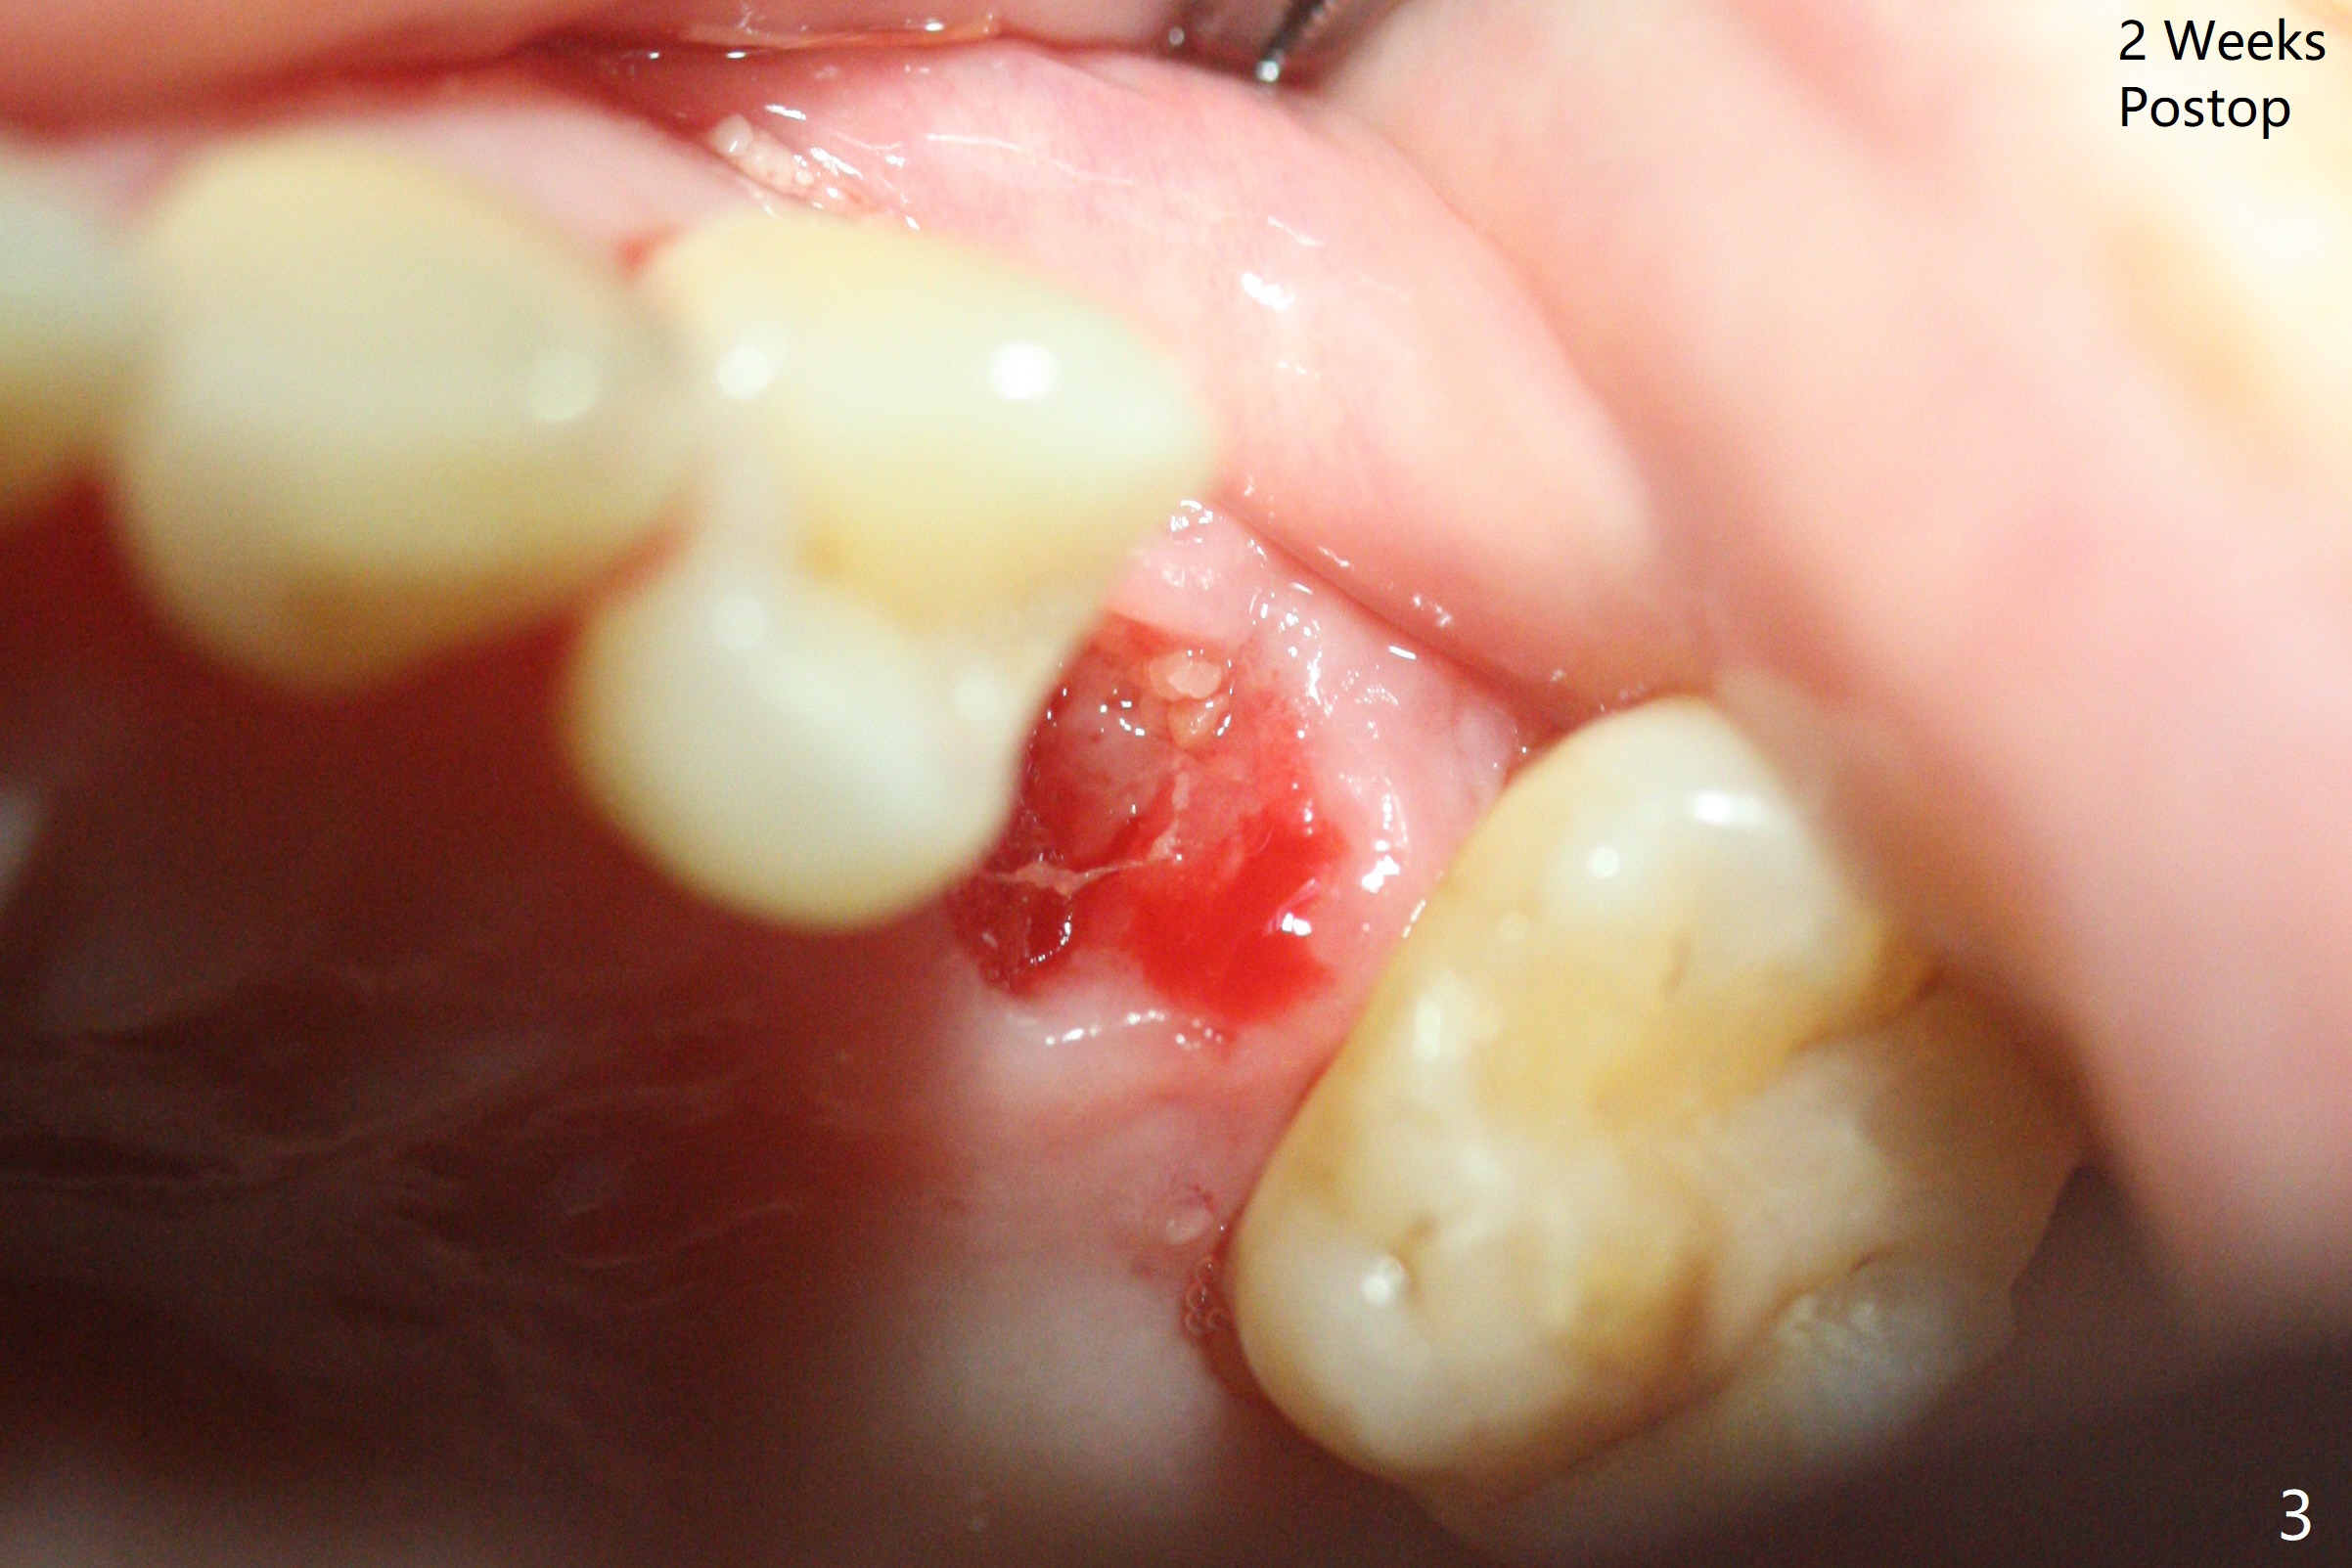

术后二周牙周敷料松动,取出后,伤口尚可(图三)。可能病人用右侧咀嚼,造成右上两个双尖牙松动疼痛,拔出后即刻种植修复,之后她能在右侧咀嚼,而食物撞击左上拔牙创疼痛,无法吃饭。术后三个月左上7疼痛,瘘道,插入牙胶尖(图四:*),根周阴影。其实腭侧根纵裂(图四,五:<),三个月已经发生(图二),可以即刻种植(图六),与5延期种植同时进行,使用导板。